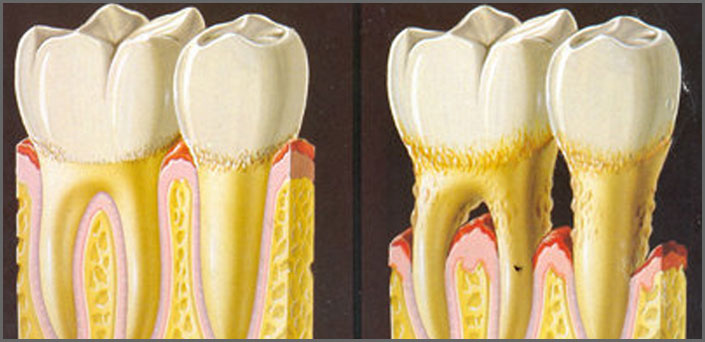

- Ουλίτιδα είναι η φλεγμονή μόνο των ούλων, αποτελεί την αρχική μορφή της περιοδοντικής νόσου και αν δεν θεραπευτεί έγκαιρα μεταπίπτει σε περιοδοντίτιδα.

- Περιοδοντίτιδα είναι η εξάπλωση της φλεγμονής κάτω από τα ούλα που προσβάλλει τους ιστούς που συγκρατούν τα δόντια, με αποτέλεσμα τα δόντια να χάνουν τη στήριξή τους, να αποκτούν κινητικότητα και πολλές φορές να καταλήγουν σε εξαγωγή. Η περιοδοντίτιδα αποτελεί την κύρια αιτία απώλειας δοντιών στους ενήλικες.